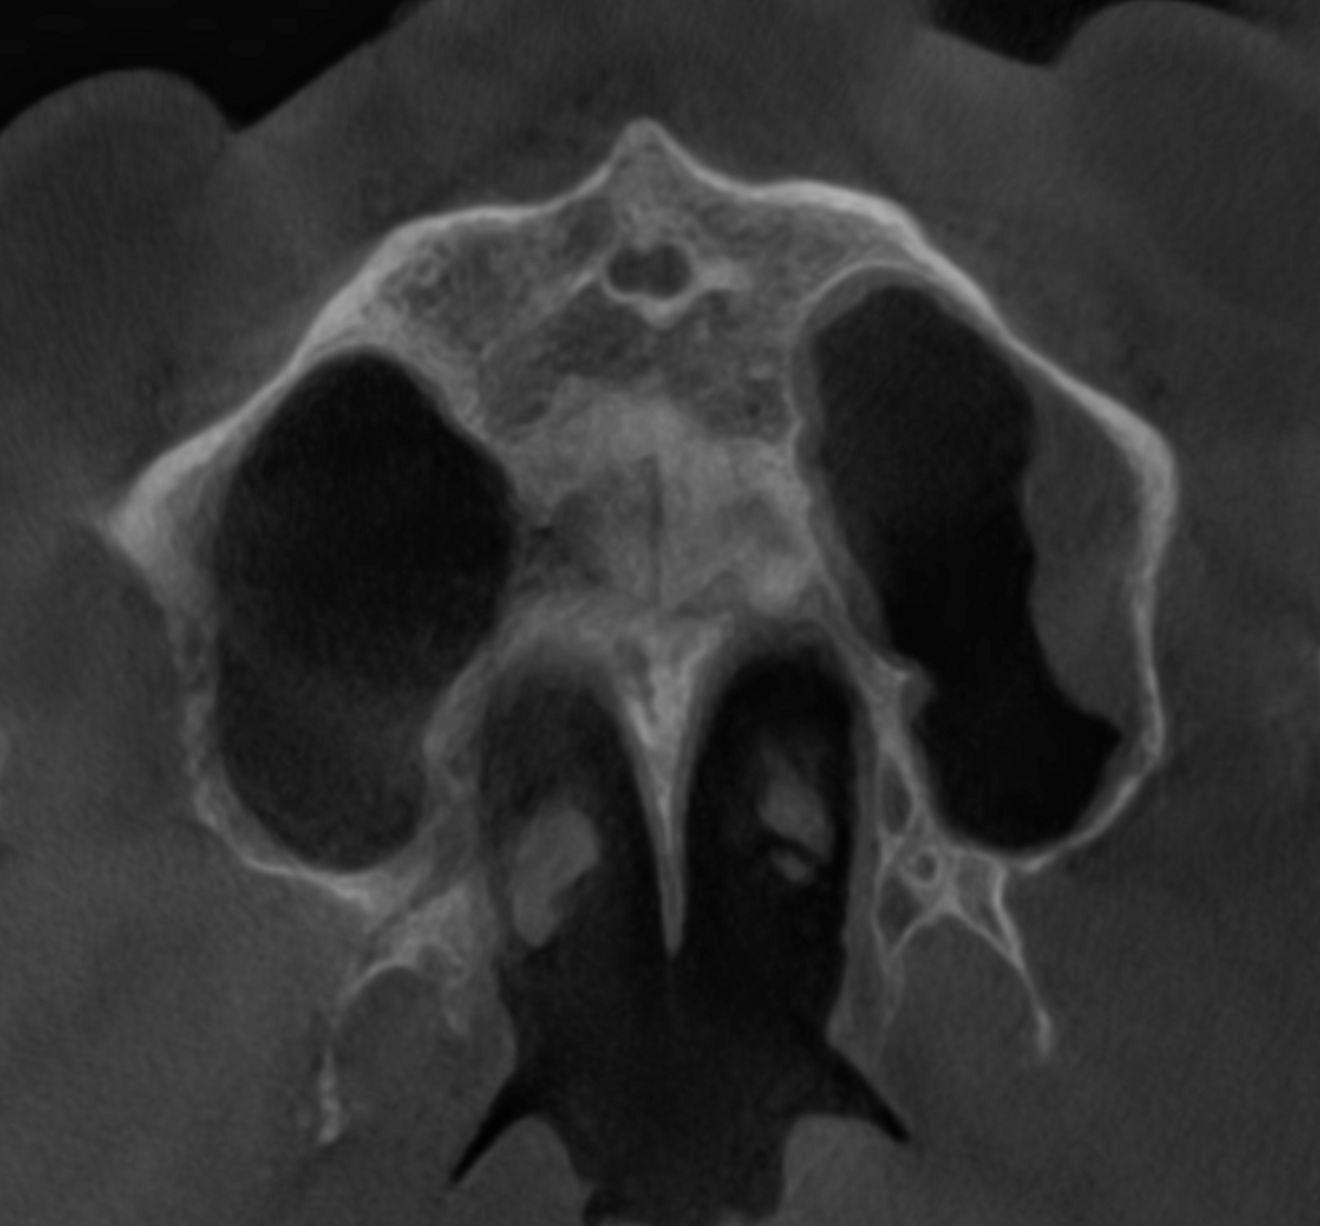

Fig. 3: Large-volume CBCT scan, frontal cross-section showing increased radiopacity in the paranasal sinus area.

The extent of the inflammation was shocking (Figs. 2a & b). Not only the maxillary sinus (Fig. 3) but the ethmoid and sphenoid sinuses too were involved, and the inflammation had spread towards the right cavernous sinus as well (Fig. 4). At this point, extraction may have been the first choice for most dental clinicians, but we had to keep in mind that invasive treatment may have increased the risk of cavernous sinus thrombosis, a potentially avoidable possibility. There are very few circumstances under which a dental procedure can cause very severe or even lethal consequences, but this case approached such a situation.